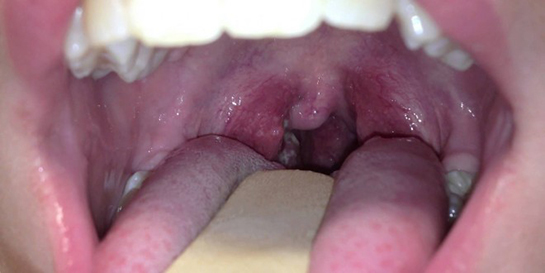

Boğaz İltihabına Ne İyi Gelir?

Boğaz iltihabı, genellikle viral veya bakteriyel enfeksiyonlar sonucu ortaya çıkan yaygın bir sağlık sorunudur. Bu makalede, boğaz iltihabının belirtileri, nedenleri ve tedavi yöntemleri üzerinde durulacak, ayrıca bu duruma iyi gelen doğal ve tıbbi yöntemler ele alınacaktır. Boğaz İltihabının Belirtileri Boğaz iltihabının belirtileri kişiden kişiye değişiklik gösterebilir. Ancak genel olarak aşağıdaki belirtiler sıkça görülmektedir: